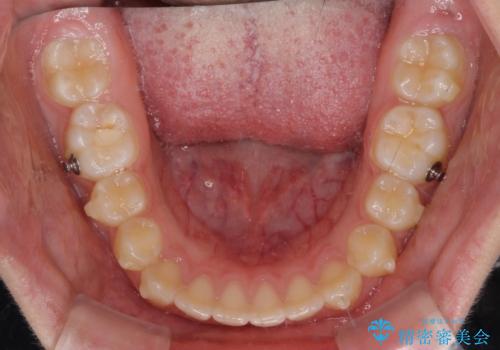

- ヨーロッパにてインビザライン矯正を始めたものの、日本に転居することになり、治療の継続を希望して来院された患者様です。

治療計画に無理がなく、現地担当医と速やかに連絡が取れるとのことで、インビザライン社での転医手続きを行い、継続して治療を行うこととしました。

舌の突出癖により、上下前歯が非接触となっていたため、トレーニングを徹底的に指導し、安定した咬み合わせにより終了させることができました。